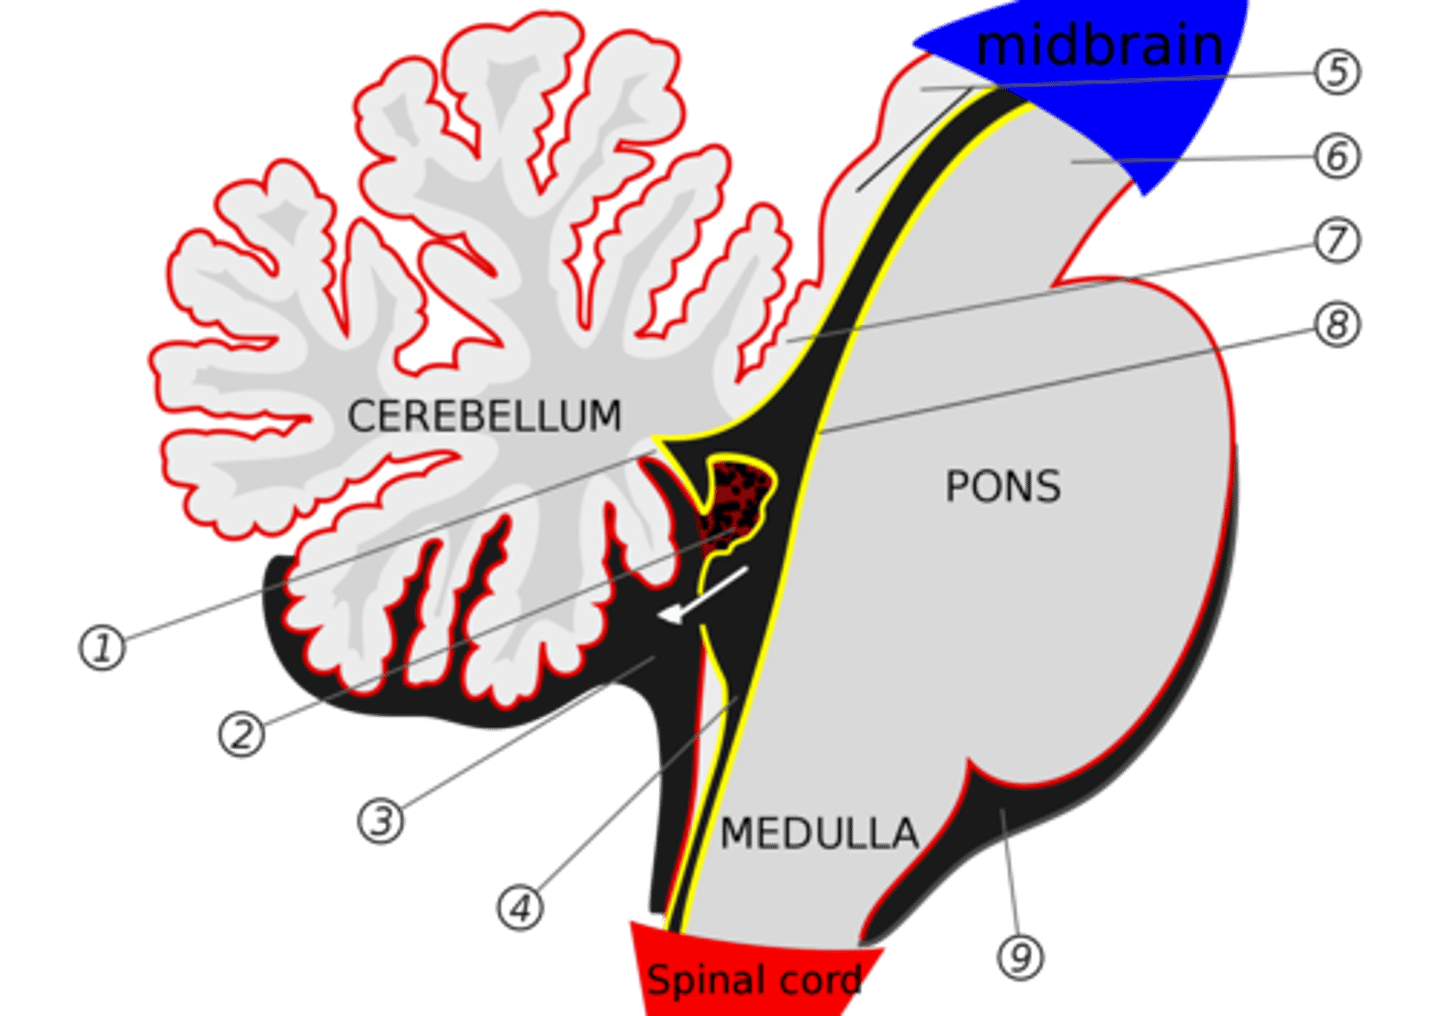

What are the structures of the brainstem?

1. mesencephalon (midbrain)

2. pons

3. medulla oblongata

What is the tectum?

roof of the midbrain

What is the tegmentum?

floor of midbrain

What are the fibers of the tegmentum?

ascending fibers

What is the crus cerebri?

part of the cerebral peduncles which contain descending tracts

What are the fibers of the crus cerebri?

descending fibers

What leaves the peduncular fossa?

CN III

What notable structures are on the dorsal surface of the mesencephalon (tectum)?

1. superior colliculi (right and left)

2. inferior colliculi (right and left)

image -- 5

What other notable structure should you see if you see two red nuclei?

"if you see two red nuclei you're at the superior colliculus level"

Where does CN III exit the brainstem?

interpeduncular fossa (ventral surface)

Where does CN IV exit the brainstem?

inferior colliculus (dorsal surface)

exits dorsal + caudal (posteroinferior) to nucleus

Where are the CN III and IV nuclei?

tegmentum mesencephalon

CN III -- anterosuperior

CN IV -- posteroinferior

What is the floor of the 4th ventricle?

tegmentum pons

What is the superior medullary velum?

membrane that forms the superior portion of the 4th ventricle roof

image -- 7

What is the inferior medullary velum?

membrane that forms the inferior portion of the 4th ventricle roof

image -- 1